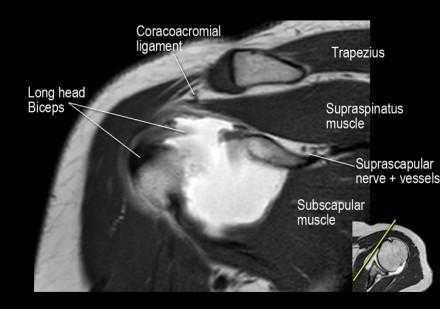

Нормальная корональная анатомия плечевого сустава и контрольный список

- обратите внимание на надлопаточный нерв и сосуды (suprascapular nerve and vessels)

- изучите верхний комплекс двуглавой мышцы и суставной губы, поищите подгубный карман илм SLAP-повреждение

- поищите скопление жидкости в подакромиальной сумке и повреждение сухожидия надостной мышцы